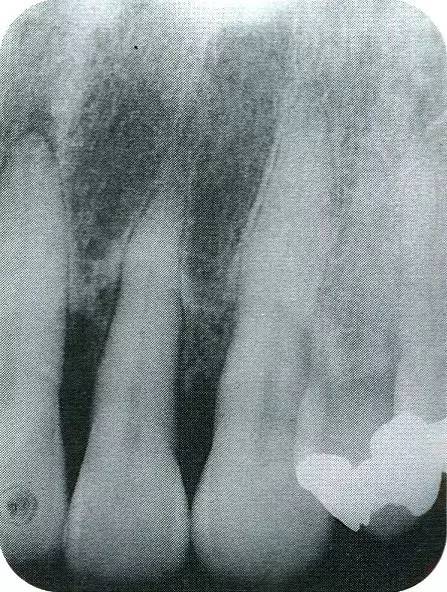

▲圖7-7  術(shù)前,術(shù)后的x片。確認(rèn)出現(xiàn)骨再生,牙槽嵴硬線。